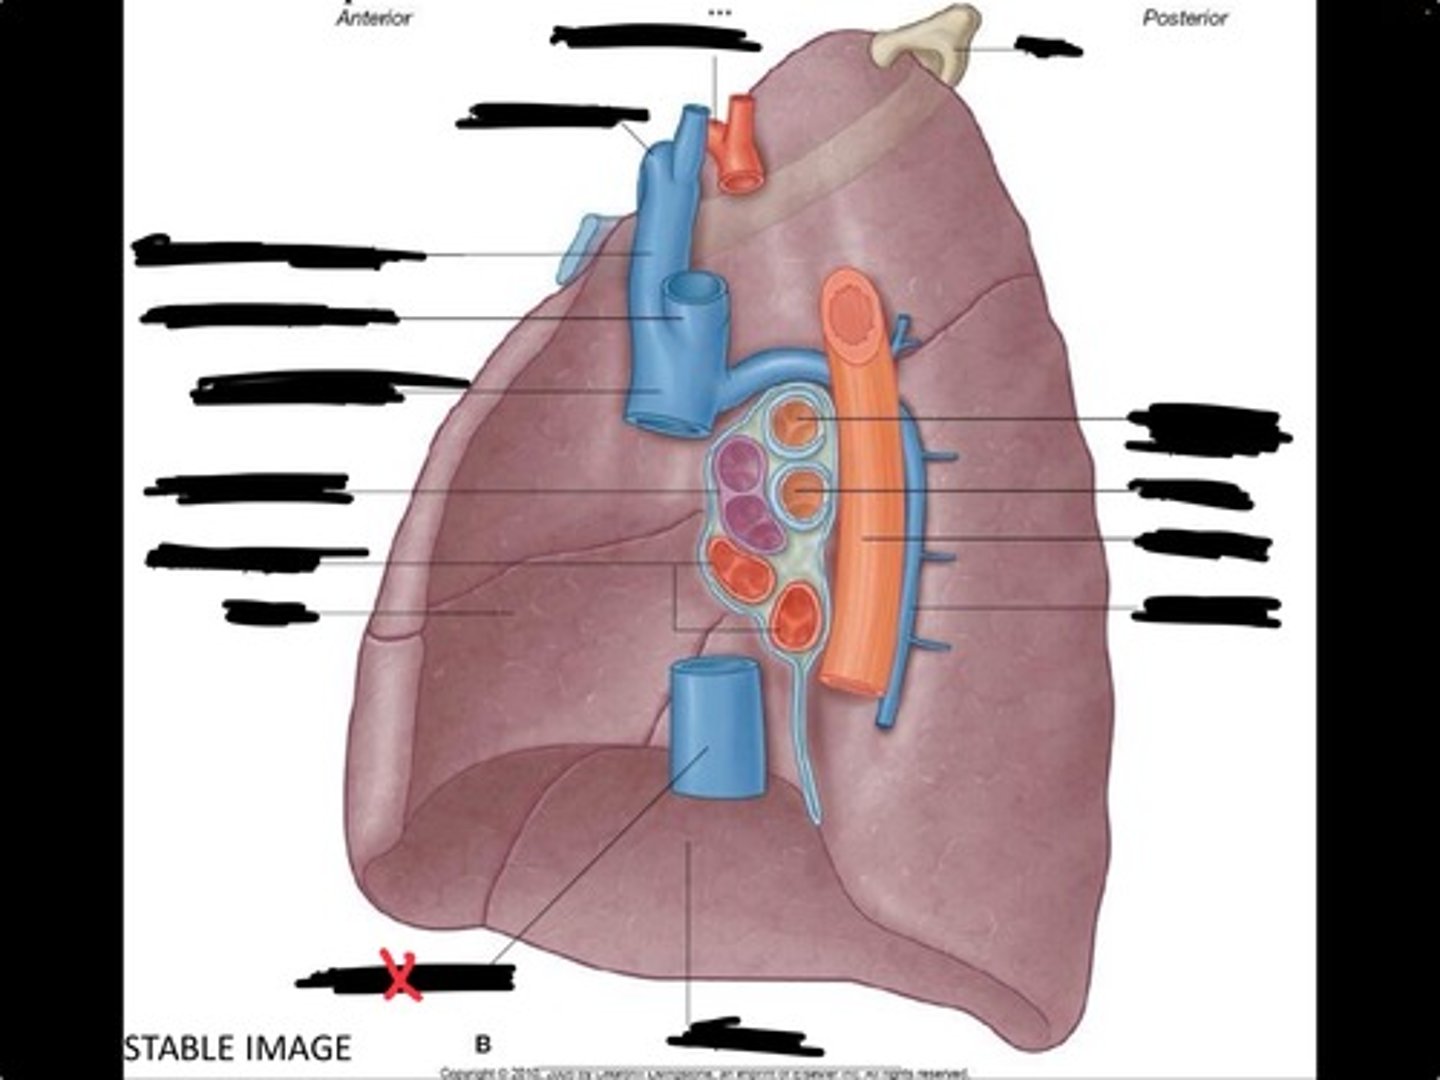

Inferior vena cava

Superior vena cava

Subclavian vein

Right bracheocephalic vein

Subclavian artery

Esophagus

Bronchus

Rib 1

Left subclavian artery

Left brachiocephalic vein

Aortic arch

Pulmonary artery

Pulmonary vein

Heart

Left brachiocephalic vein

Azygos vein

Esophagus

Bronchus